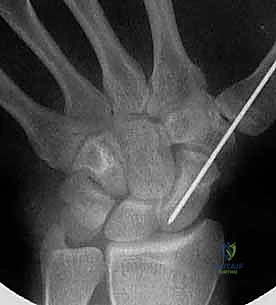

تقنية "التثبيت عن طريق الجلد" (Percutaneous Fixation) هي إجراء جراحي طفيف التوغل (Minimally Invasive). بدلاً من فتح الرسغ، يقوم الجراح بإجراء ثقب صغير جداً في الجلد (لا يتجاوز 3-5 مليمترات). من خلال هذا الثقب، وباستخدام جهاز الأشعة السينية المباشر في غرفة العمليات (C-arm Fluoroscopy)، يتم إدخال سلك توجيهي دقيق، ثم يتم إدخال مسمار خاص يسمى "مسمار ضغط بدون رأس" (Headless Compression Screw) مثل مسمار هيربرت (Herbert Screw).

هذا المسمار العبقري يتم دفنه بالكامل داخل العظم (تحت سطح الغضروف حتى لا يحتك بالمفاصل الأخرى)، ويتميز بوجود أسنان لولبية (Threads) في طرفيه بمسافات مختلفة. هذا التصميم يجعله يسحب طرفي الكسر ويضغطهما معاً بقوة هائلة (Compression)، مما يحفز التئام العظم بسرعة فائقة ويمنع أي حركة بين طرفي الكسر.

1. المدخل البطني (Volar Approach): من جهة راحة اليد. يُستخدم عادة لكسور منطقة الخصر (المنتصف).

2. المدخل الظهري (Dorsal Approach): من ظهر اليد. يُعتبر الأفضل لكسور القطب القريب، حيث يوفر مساراً أسهل للوصول إلى هذا الجزء العميق بمحاذاة المحور الميكانيكي للعظم.